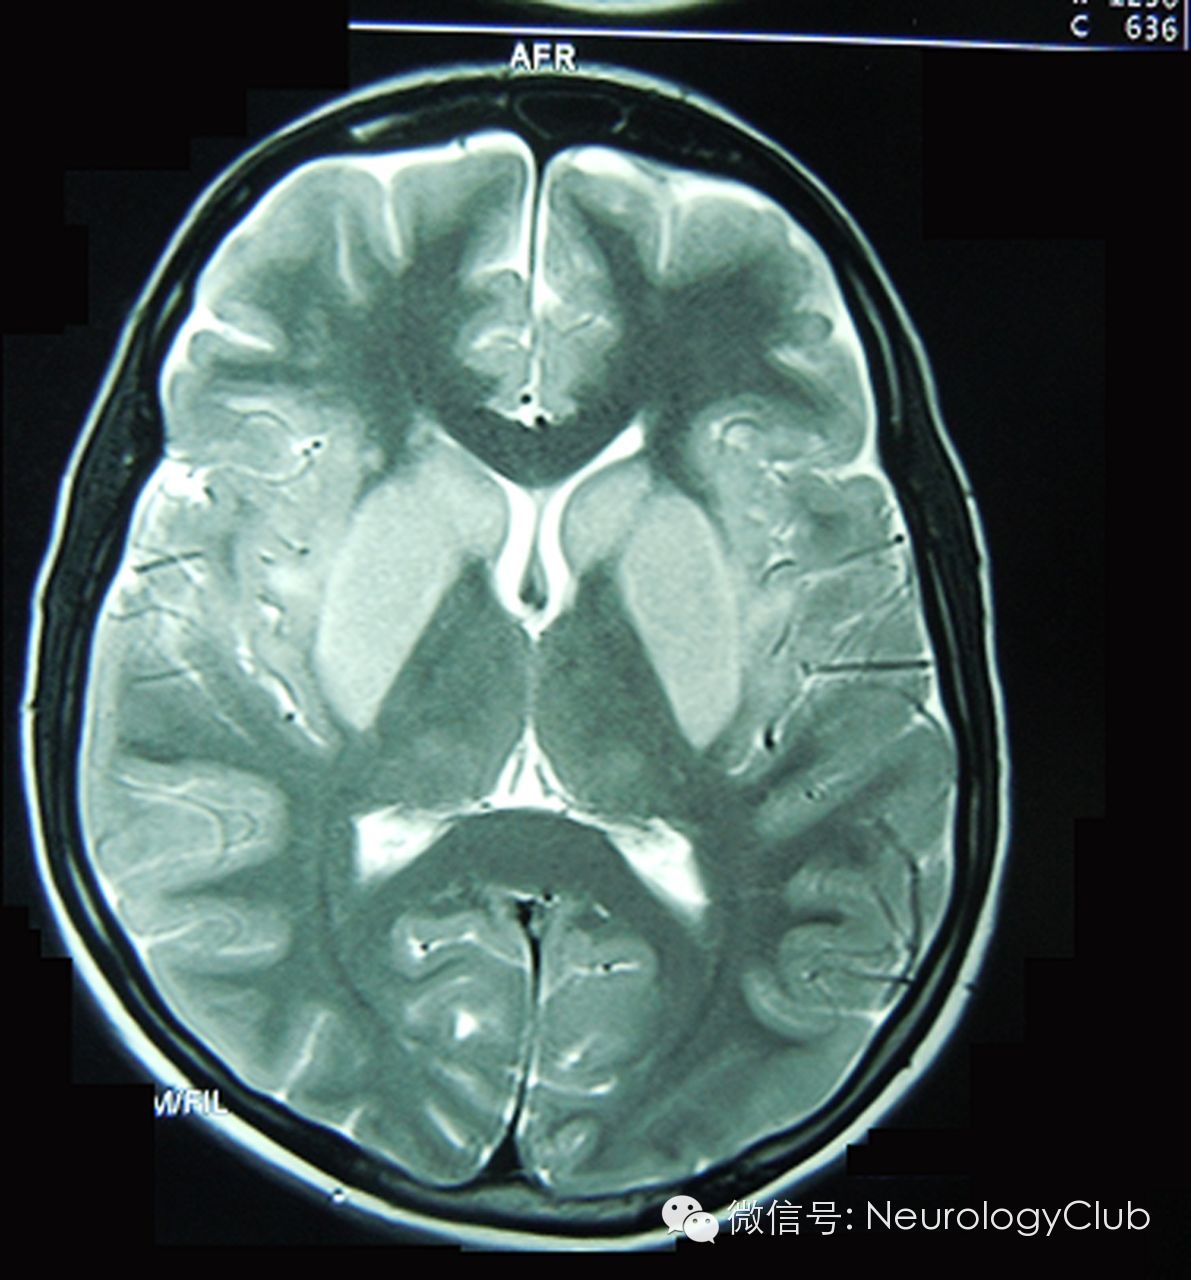

图3:MRI可见双侧尾状核和豆状核T2高信号

28岁女性,既往体健,因为家庭内部纠纷食用嘉兰块茎准备结束自己的生命,6小时后患者出现腹痛、腹泻及大量呕吐。入院时,患者病情平稳,予活性炭并对症治疗。起初症状有所改善,但在第5天时,出现全面强直-阵挛发作,查血钙偏低0.9mmol/L(1.1-1.4)。予静脉补钙并和抗惊厥药物,患者发作得到了控制。第7天时,患者意识水平下降,Glasgow昏迷评分6分,无其他局灶性神经系统体征。全血计数,动脉血气分析,尿常规,血沉,血清C-反应蛋白,尿素,电解质,葡萄糖,血氨,钙和镁等均正常。血清转氨酶短暂轻度升高:天门冬氨酸氨基转移酶(AST)278U/L(1-31),丙氨酸氨基转移酶(ALT)216 U/L(5-35)。头颅CT,脑脊液化验,腹部盆腔超声均正常。EB病毒,巨细胞病毒,日本脑炎病毒,单纯疱疹病毒血清学阴性。脑电图可见双侧弥漫慢波,提示脑病。MRI见双侧基底节区(尾状核和豆状核)T2高信号。患者住进ICU行支持治疗。病程中出现脱发。第15天时,Glasgow昏迷评分升至11分,随访至报道时,病情平稳。

患者头颅MRI显示双侧基底节区尾状核和豆状核T2高信号,符合中毒性脑病的特征,更加支持嘉兰引发的脑病。丘脑区域未受累。壳核和苍白球富含线粒体,神经递质和其他化学成分。因此,代谢极度活跃,也很容易遭受代谢性和中毒性损伤。中毒性和代谢性脑病的基底节区病灶多广泛且对称,正如我们这位患者。此外,类似相对孤立的基底节区病灶不伴有丘脑受累仅见于少数原因的中毒性脑病,如高血氨和低血糖,而这些原因已被排除。感染性疾病也可有基底节区受累,但通常为片状不对称性。还有一种可能是患者服用了出嘉兰外的另一种神经毒性药物。